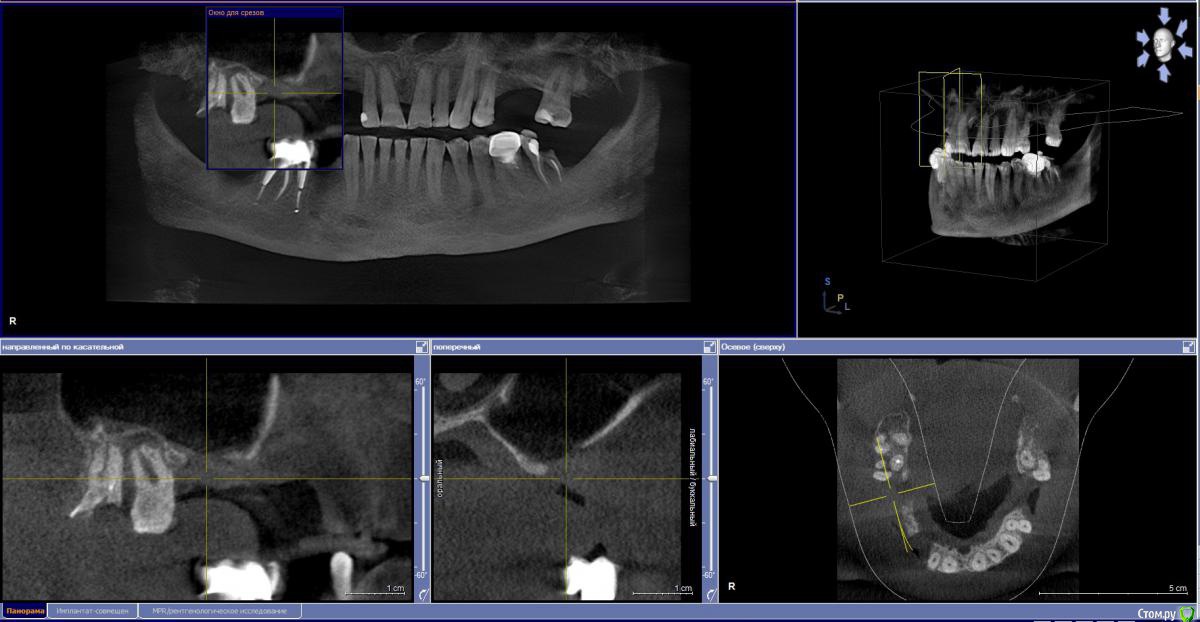

kamranchick Опубликовано 4 мая, 2018 Поделиться Опубликовано 4 мая, 2018 Обратился пациент после очередной халтуры которыми радуют меня коллеги из соседних клиник)фотопротокол ни как у Сашки Гудкова но более-менее понятно))Обратился пациент, в соседней клинике удаляли зуб, корень протолкнули в пазуху, далее пациент попал в ЧЛХ, там сделали радикальную гайморотомию, все достали, и вот попал пациент ко мне, так как в другой клинике сказали что у вас тут залу*а, а не кость, ну и погнали.1. пытался остро отслоиться, перфа на перфе, закрывал prf, мембранами, губками, стики бон + синус имплантация. ожидание 9 месяцев2. Пластика мягких тканей ожидание 2 месяца. 13 Ссылка на комментарий

kamranchick Опубликовано 4 мая, 2018 Автор Поделиться Опубликовано 4 мая, 2018 а рентген?))Есть кт до, и есть панорамник)завтра могу это все скинуть если интересно Ссылка на комментарий

Kazankov.Egor Опубликовано 5 мая, 2018 Поделиться Опубликовано 5 мая, 2018 Обратился пациент после очередной халтуры которыми радуют меня коллеги из соседних клиник)фотопротокол ни как у Сашки Гудкова но более-менее понятно))Обратился пациент, в соседней клинике удаляли зуб, корень протолкнули в пазуху, далее пациент попал в ЧЛХ, там сделали радикальную гайморотомию, все достали, и вот попал пациент ко мне, так как в другой клинике сказали что у вас тут залу*а, а не кость, ну и погнали.1. пытался остро отслоиться, перфа на перфе, закрывал prf, мембранами, губками, стики бон + синус имплантация. ожидание 9 месяцев2. Пластика мягких тканей ожидание 2 месяца.К кому сходить на мягкие ткани? Посоветуйте пожалуйста. Ссылка на комментарий

Eddie Опубликовано 7 мая, 2018 Поделиться Опубликовано 7 мая, 2018 У вас тут в области 13 и 15 диаметры имплантатов 3.5(3.8)? Выдержат такую конструкцию? Ссылка на комментарий

kamranchick Опубликовано 7 мая, 2018 Автор Поделиться Опубликовано 7 мая, 2018 У вас тут в области 13 и 15 диаметры имплантатов 3.5(3.8)? Выдержат такую конструкцию?ну да, а что ей будет) связанная конструкция, на израиле 3.75, служат) Ссылка на комментарий